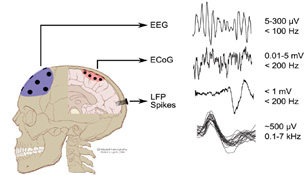

The electromagnetic spectrum is divided up into a number of categories. The wireless radiation emitted by smart meters is known as radiofrequency radiation (RF) or microwave radiation. Smart meter radiation falls near cell phone radiation on the electromagnetic spectrum. At the left end, you find what is known as extremely low frequency, or ELF, radiation.

This is the radiation that our cells use to communicate with each other and that is used in nerve transmission. The 60 Hertz of your home wiring is ELF radiation, and is generally a continuous, smooth wave. The dirty electricity that is generated by smart meters is also ELF radiation, but this ELF radiation is pulsed and spiky rather than continuous and smooth.

Our bodies are electromagnetic. This is why our brains work and why our heart beats and our muscles contract. As Michio Kaku, CUNY physicist, futurist, and author says, “Our brains are milliwatt transmitters.” Nature, the premier publication in science, notes: “There are striking analogies between signaling networks in biological systems and electronic circuits.”

Electromagnetic fields of all kinds (radiofrequency/microwave, dirty electricity) knock calcium ions off the cell membrane. This accounts for the wide variety of effects seen with exposure to smart meters because calcium acts like a neurotransmitter. Thus, your heart, your gut, your brain, your muscles, and your hormones can be affected. In general, the first place that is harmed is the place where you have the least resistance. Over time, various other organ systems will be harmed. We go into this in great detail on our Health: The Science page.